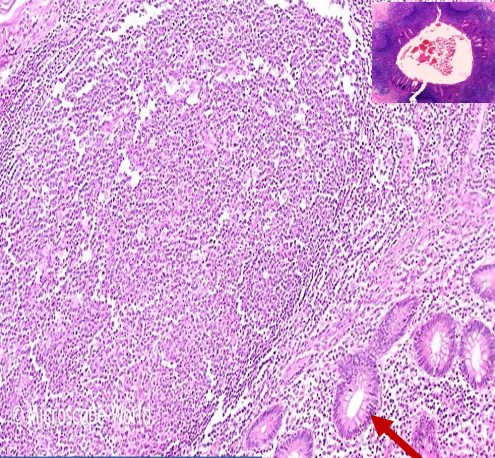

24

Q

Diagnosis

Describe

Arrows

Behaviour

A

Adenocarcinoma of colon

MALIGNANT TUMOR formed of irregular acini infiltrating the submucosa and muscle layer. Malignant cells vary in size and shape

Red: normal mucosal glands Black: Malignant glands

Malignant